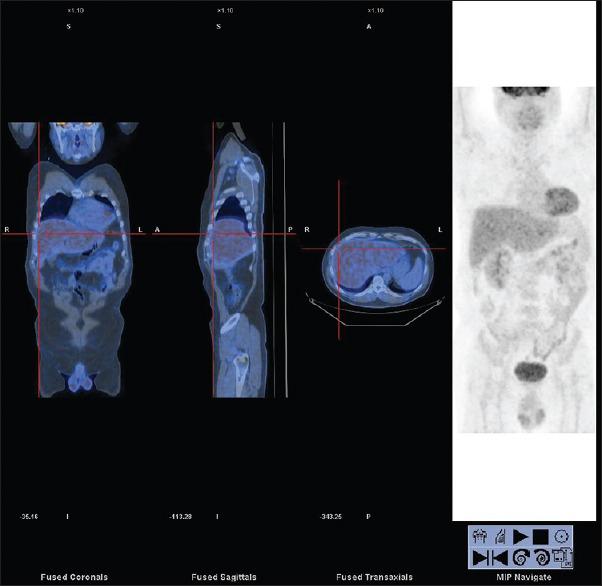

This case report explores the potential role of FDG PET/CT in HIV -associated systemic non-Hodgkin's lymphoma (HIV-NHLs). In our locality, there are a cumulative total of 5523 reported HIV infections cases since 1984. We reported a case of HIV-related Burkitt's lymphoma (BL) and a case of diffuse large B-cell lymphoma (DLBCL) that underwent PET/CT examination in our PET centre. In HIV-NHLs patients, we must be reminded that not all hypermetabolic foci represent lymphomatous lesions. There is a close correlation between the pattern of lymphoid tissue activation in FDG PET/CT and HIV progression in patients without HIV-related malignancy. The unique patterns of lymphoid tissue activation observed in HIV-infected patients have great clinical implications. Secondly, HIV-infected patients are prone to suffer from opportunistic infections due to immunosuppression, particularly in those with high levels of HIV viral loads. FDG PET/CT cannot reliably differentiate metabolic active lymphoma from other benign diseases such as inflammation in the context of low CD4 count and high viral loads. In those cases, benign markedly hypermetabolic foci can be erroneously interpreted as lymphoma, particularly in those normal-sized lymph nodes. Furthermore, FDG PET/CT may be useful for assessing the efficacy of HAART in suppressing HIV replication and detecting its complication such as lipodystrophy. FDG PET/CT may play a potential useful role in staging and management of HIV -associated systemic non-Hodgkin's lymphoma. Plasma variables such as viral loads and CD4 count must be taken into account during image interpretation. FDG PET/CT as a potential useful tool for diagnosis, treatment response assessment and disease relapse detection in HIV -associated systemic non-Hodgkin's lymphoma worth to be further explored.

本病例报告探讨了氟代脱氧葡萄糖正电子发射断层扫描/计算机断层扫描(FDG PET/CT)在人类免疫缺陷病毒相关系统性非霍奇金淋巴瘤(HIV-NHLs)中的潜在作用。自1984年以来,在我们当地累计报告了5523例HIV感染病例。我们报告了1例HIV相关的伯基特淋巴瘤(BL)和1例弥漫性大B细胞淋巴瘤(DLBCL),这2例患者均在我们的PET中心接受了PET/CT检查。对于HIV-NHLs患者,我们必须注意,并非所有高代谢灶均代表淋巴瘤性病变。在无HIV相关恶性肿瘤的患者中,FDG PET/CT中淋巴组织激活模式与HIV进展密切相关。在HIV感染患者中观察到的独特淋巴组织激活模式具有重要的临床意义。其次,由于免疫抑制,HIV感染患者容易发生机会性感染,尤其是那些HIV病毒载量高的患者。在CD4计数低和病毒载量高的情况下,FDG PET/CT无法可靠地区分代谢活跃的淋巴瘤与其他良性疾病,如炎症。在这些情况下,良性的明显高代谢灶可能会被错误地解释为淋巴瘤,尤其是在那些大小正常的淋巴结中。此外,FDG PET/CT可能有助于评估高效抗逆转录病毒治疗(HAART)在抑制HIV复制方面的疗效,并检测其并发症,如脂肪代谢障碍。FDG PET/CT在HIV相关系统性非霍奇金淋巴瘤的分期和管理中可能发挥潜在的有用作用。在图像解读过程中,必须考虑病毒载量和CD4计数等血浆变量。FDG PET/CT作为一种潜在的有用工具,在HIV相关系统性非霍奇金淋巴瘤的诊断、治疗反应评估和疾病复发检测方面值得进一步探索。